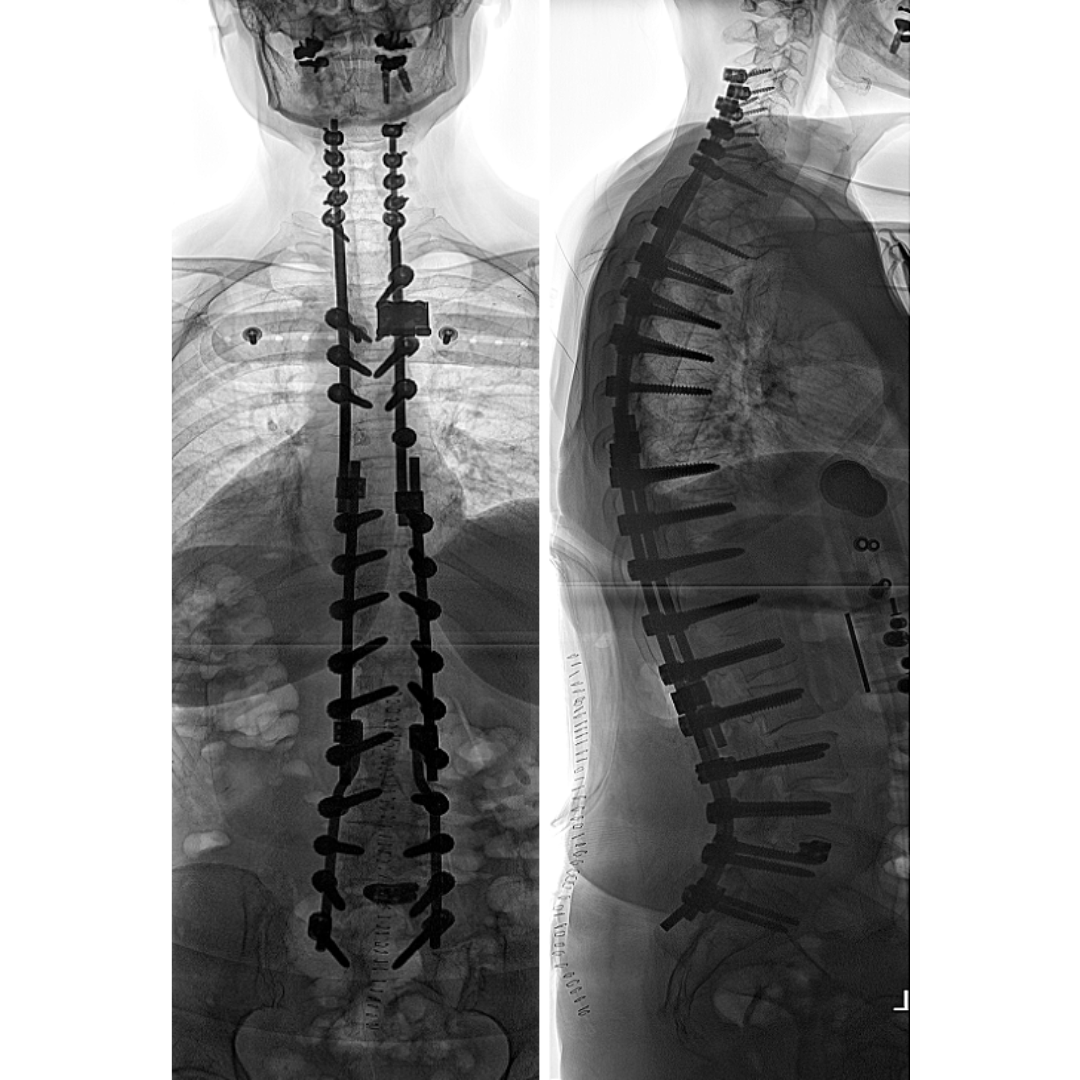

De behandeling van een degeneratieve scoliose begint altijd met niet-operatieve maatregelen. Als bot ontkalking in het spel is moet hierop, in overleg met de huisarts, actie worden ondernomen. In het verdere traject is vrijwel altijd de medewerking van de patiënt van het allergrootste belang. Soms is afvallen noodzakelijk, vaak zal er met de fysiotherapeut/Schroth therapeut hard getraind moeten worden om de stabiliteit van de rug en de romp te verbeteren. Over de rol van een korset ter ondersteuning van de romp bestaat veel verschil van inzicht, in ieder geval is een korset behandeling veeleisend, oncomfortabel, en bestaat het risico van verdere achteruitgang van de spier conditie. Toch kunnen sommige mensen van een korset veel plezier hebben, het zal dan meestal slechts een beperkt aantal uren per dag (of alleen ‘s nachts!) moeten worden gedragen. Het is daarnaast van groot belang om te weten dat de fase van instabiliteit, waarin de klachten zeer heftig kunnen zijn, in de meeste gevallen weer over gaat, waarna de rug vaak wel stijver, maar veel minder pijnlijk kan zijn geworden. Echter, als een degeneratieve scoliose toeneemt, kan dit de kwaliteit van leven zeer ernstig bedreigen, en zijn soms uitgebreide operatieve behandelingen noodzakelijk (Figuur 3).4

Hoewel de risico’s van dergelijke ingrepen vrij groot zijn, en het herstel langdurig, kan hiermee uiteindelijk wel een verbetering in het functioneren in het dagelijks leven worden verkregen. Vanzelfsprekend moet in een gesprek met de operateur de voor- maar zeker ook de nadelen van een dergelijke grote operatie worden besproken.